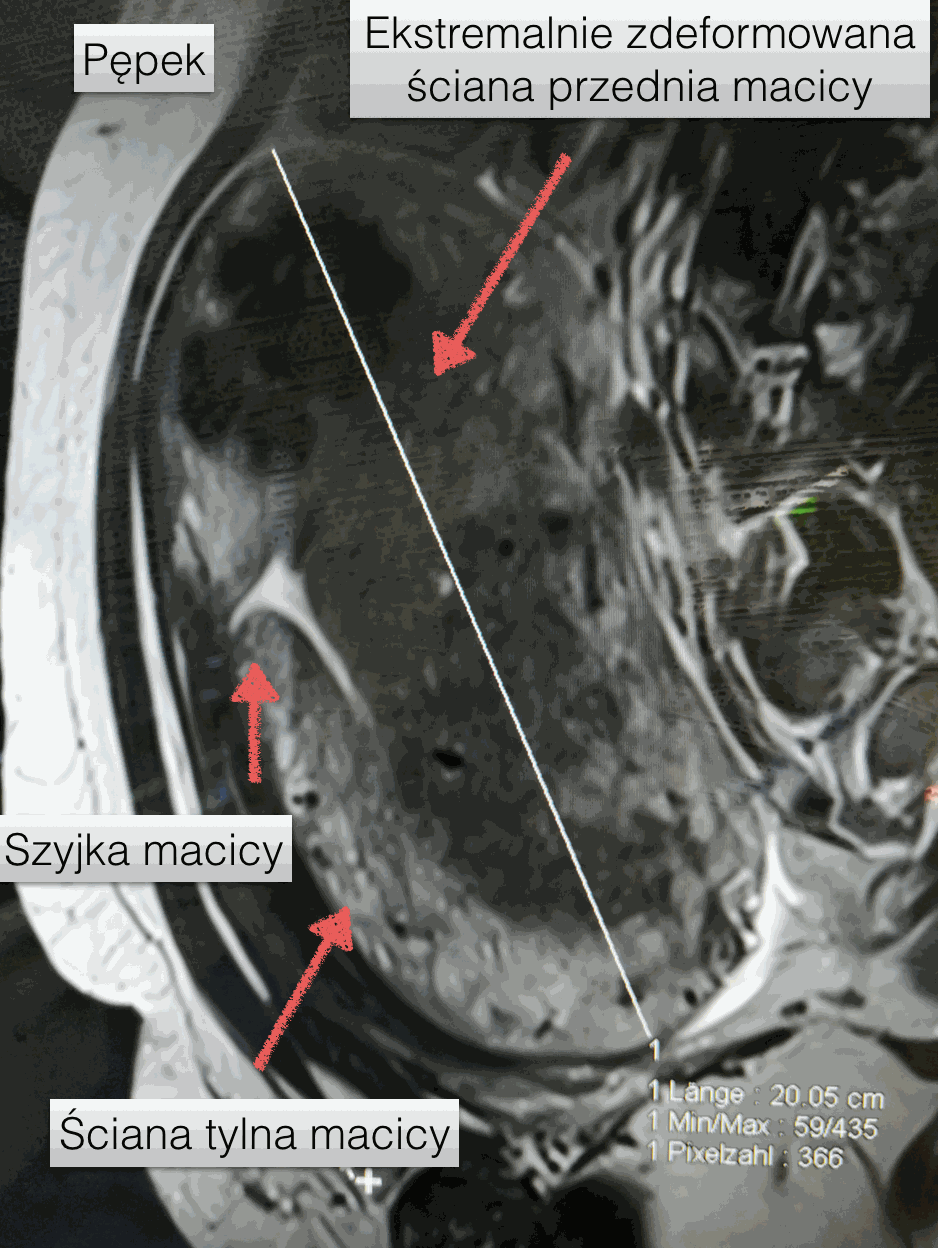

Pacjentka ma 44 lata, pochodzi z Afryki, aktualnie mieszka w Wielkiej Brytanii. Od 14 lat stara się bezskutecznie o poczęcie. O adenomiozie jeszcze nie słyszała. Podczas badania nie była możliwa ocena szyjki macicy, która powędrowała do góry i znajdowała się ponad spojeniem łonowym! Na pierwszy rzut oka beznadziejny przypadek. Jeśli jednak dokładniej się przyjrzymy, to szyjka i ściana tylna macicy są w całkiem niezłym stanie. Ściana tylna i dno macicy są niemal całkowicie zmienione przez adenomiozę i liczne mięśniaki macicy mięśniaki.  Macica sięgała do pępka i mierzyła ponad 20 cm!